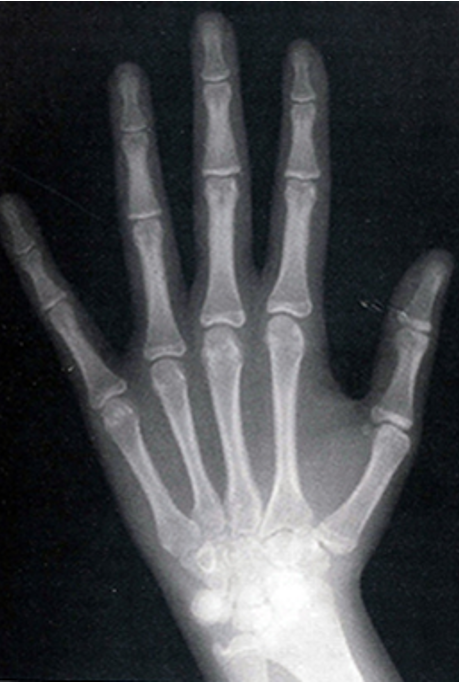

hand wrist radiograph

outline hand wrist radiographs

ulnar sesamoid bone ossifies at the start of pubertal growth spurt

median bone maturity stage for each chronological age and sex identified and compiled as atlases

limited value

is not really done anymore